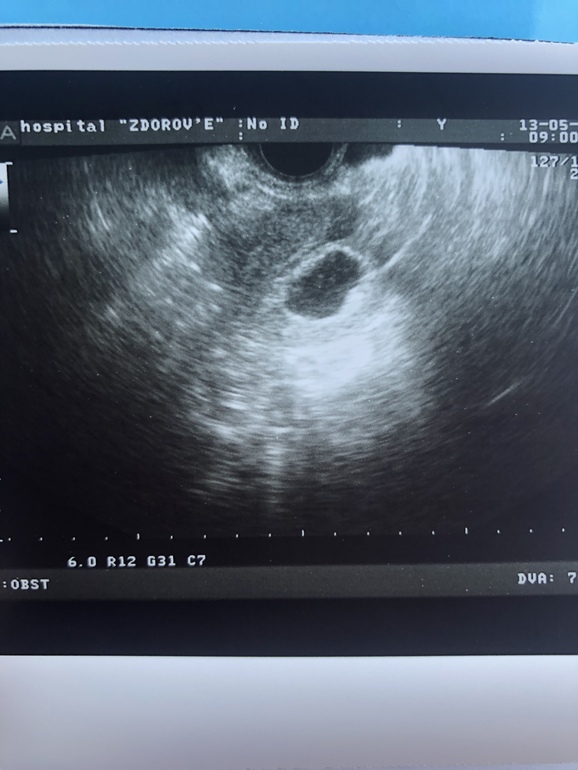

Девочки, сегодня 36 ДПП (5.1 эмбриональных недель)- УЗИ показало плодное яйцо неправильной формы 22*13мм., эмбриона нет, желточного мешочка тоже((. У кого нибудь было что-то похожее? Чем все закончилось? Есть ли смысл ждать чуда?

К сожалению нет смысла ждать.

У меня был на 28 день желточный мешок, но не было эмбриона на 30 эмбрион появился. Но к этому дню не то что эмбрион должен быть а СБ. Ждали ещё неделю, доктор сказал 10% на успех.

Но, у вас 36 день и нет даже желточного мешка. То есть у вас даже 10% нет. Тем более яйцо уже не правильной формы. Это говорит о том что оно уже погибает. У меня так было перед тем как доктор назначил МА

Честно говоря смысла в ней уже нет. У Вас яйца начало деформироваться. Это говорит о том что оно уже погибает

В том то и дело, что у большинства уже ручки с ножками начинают появляться. А тут только деформированное плодное яйцо, размер которого как назло соответствует сроку.